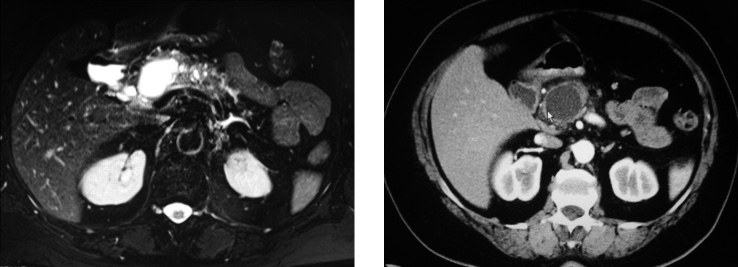

Figura 1. Immagini RM/TC della lesione cistica mucinosa intraduttale

Sulla base del referto della TC la paziente è stata sottoposta a colangio-RM (Figura 1).

Tale esame mostrava, in corrispondenza della testa-corpo pancreatica, una formazione rotondeggiante a contenuto fluido e margini netti (diametro maggiore = 33 mm). Un’altra formazione simile, plurisettata e più piccola (22 mm) era presente a livello del processo uncinato. Era evidente un’ectasia del dotto pancreatico principale con numerose estroflessioni simil-cistiche, la maggiore delle quali con diametro massimo di 8 mm. Nel corso di un ulteriore approfondimento diagnostico la paziente è stata sottoposta a colangio-pancreatografia retrograda endoscopica (ERCP) che dimostrava la presenza di una papilla aumentata di volume con aspetto adenomatoso e una stenosi del Wirsung a livello del corpo con probabile cisti in tale sede. Durante la procedura è stata effettuata aspirazione del succo pancreatico al cui interno era dimostrata un’elevata concentrazione di CA 19.9 (3.030 U/ml). L’esame istologico del campione bioptico raccolto nella papilla mostrava atipie cellulari e flogosi produttiva non specifica della mucosa intestinale.